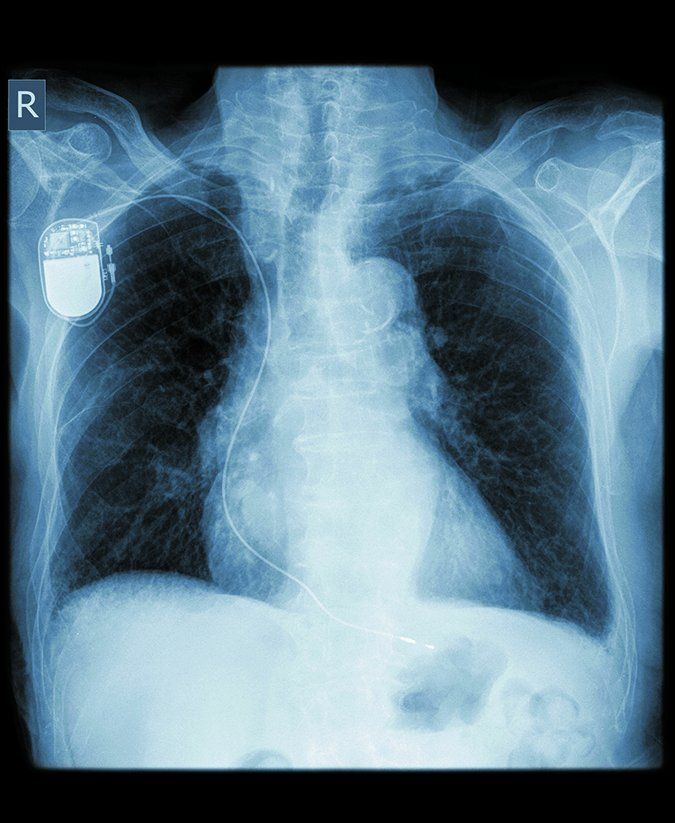

CT Scans Generally Safe for Patients with Cardiac Devices

Despite concerns that the imaging tests may interfere with your ICD or pacemaker, the FDA and health experts agree that your risks are low.

Improvements in technology are reducing the risks certain machinery and magnetic fields pose to individuals with implantable cardioverter devices (ICDs). But many ICD patients still have concerns about whether they can safely undergo computed tomography (CT) scans. These are imaging tests used to provide doctors detailed pictures of the heart muscle and the blood vessels in the heart.